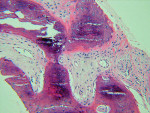

The UCSF laboratory results at 3 months after the bone graft for the Puros side was positive for sclerotic lamellar and woven bone with inflammation, no foreign material seen, 100% bone healing, and vascularisation at scale 5 (Figure 5). Puros was integrated completely into the newly formed bone, and it was impossible to distinguish any residual Puros granules. The UCSF laboratory results for the Bio-Oss side were positive for sclerotic bone with inflammation and foreign material, 20% bone healing, with vascularization at scale 5 (Figure 6 ). Bio-Oss showed slow and partial integration with easily distinguishable Bio-Oss granules at the time of investigation. The Progentix laboratory also conducted the same histological evaluation, and found less integration of Bio-Oss into the surrounding host bone at the same time point (Figure 7).